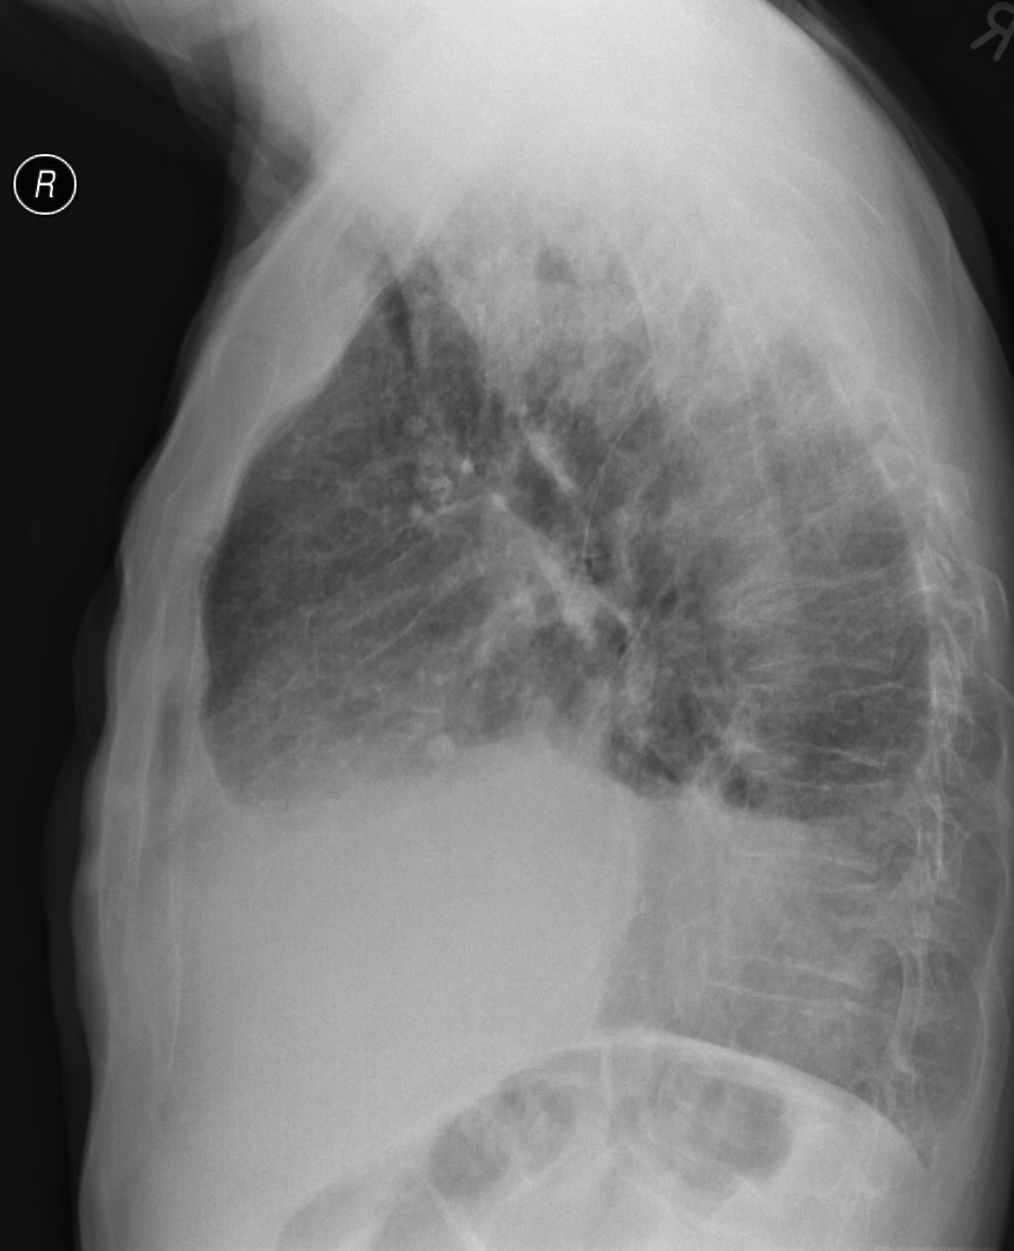

5a,b: Lung abscess. Chest radiograph, bidirectional (PA+lateral - right side near the film).

61 year old woman. Laparoscopic esophagus diverticulum resection 2 months ago. 7 cm air-fluid level with air space above: „basket sign” above the right diaphragm laterally measuring 2,5 cm in lateral diameter and 7 cm mediodorsally.